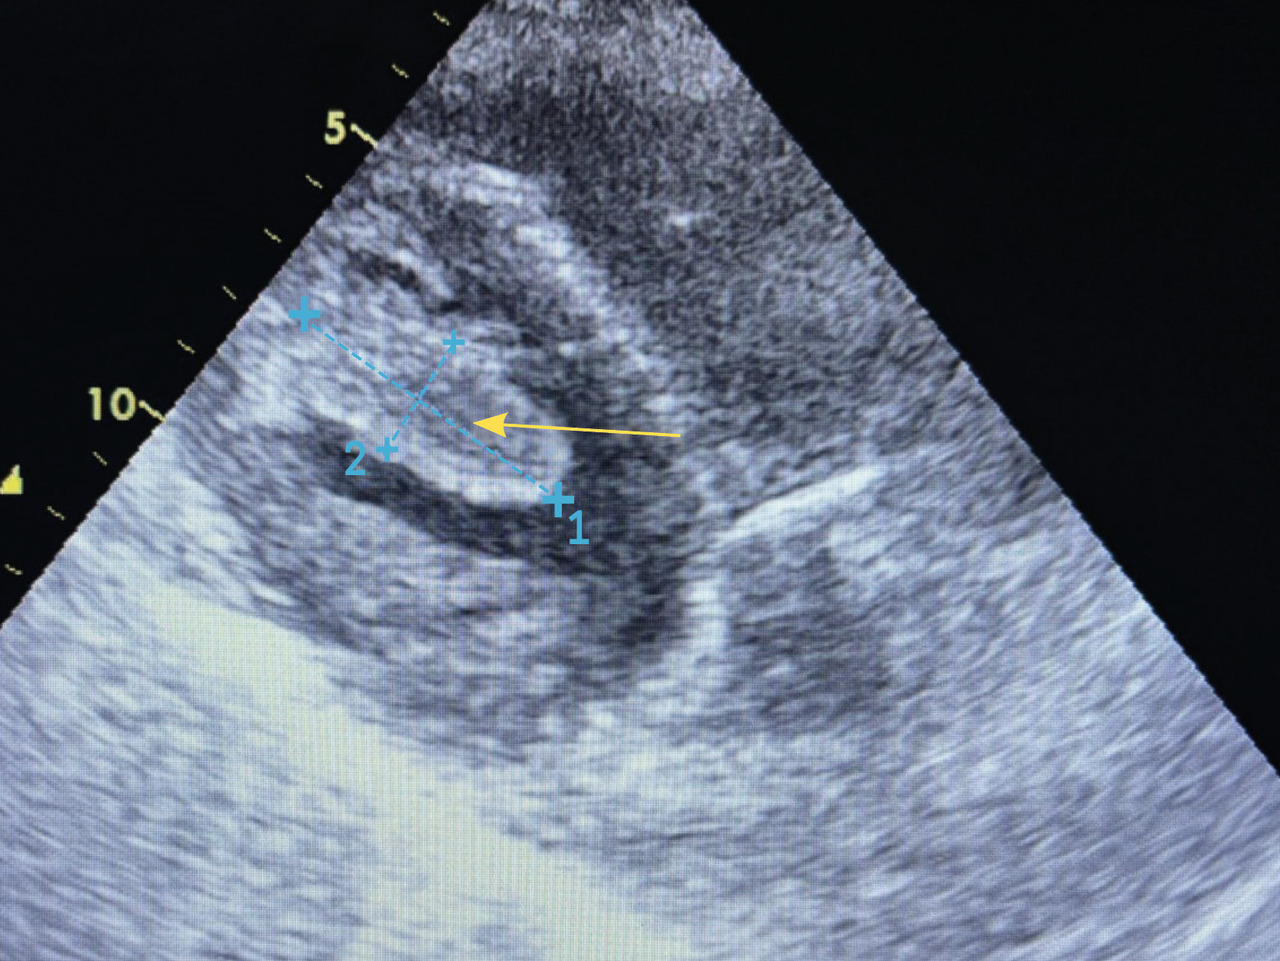

Une échocardiographie transthoracique montre la présence d’un thrombus intraventriculaire gauche (VG) apical (fig. 2), siège d’une akinésie de l’apex et une fonction globale conservée avec fraction d’éjection du VG (FEVG) estimée à 50 %.